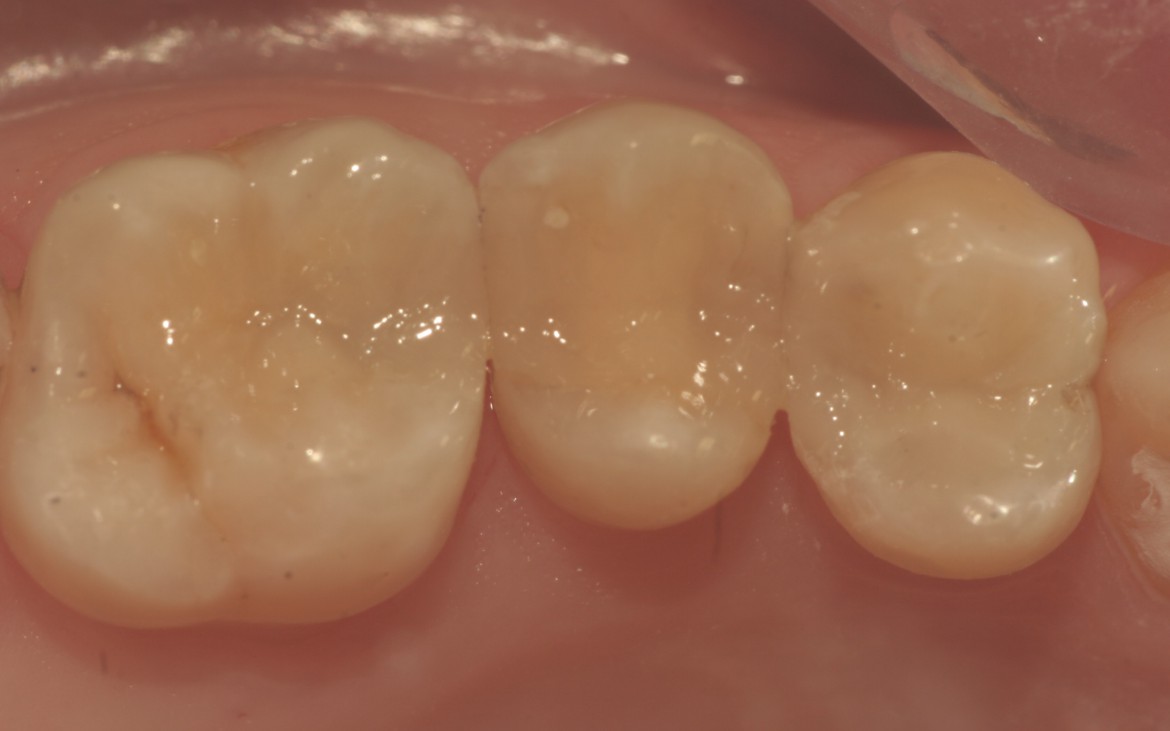

A resina composta Charisma Diamond (Heraeus Kulzer) é uma das principais representantes dessa nova geração de compósitos, apresentando como principais características o baixo escoamento, facilidade de manipulação, alta resistência, além de excelente acabamento e estética. A presença de monômeros multifuncionais proporcionam redução da contração e otimização da polimerização e formação de cadeias cruzadas, elevando a resistência do material. Clinicamente isto se traduz em economia de tempo, com a possibilidade inserção de incrementos maiores sem comprometer o resultado final da restauração, viabilizando a execução de restaurações múltiplas por setor sem modificações na técnica restauradora.

O presente caso clínico mostra a execução de restaurações múltiplas utilizando-se Charisma Diamond (Heraeus Kulzer) num mesmo tempo operatório, com inserção da resina pela técnica incremental, o que facilita a execução da escultura e a devida devolução da anatomia e da função.